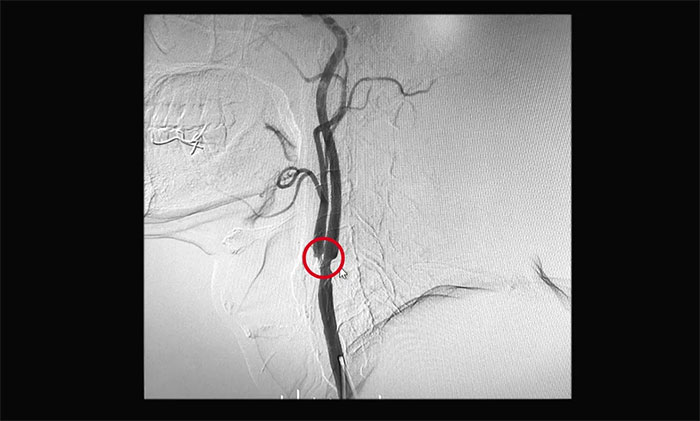

▲ 為患者開展DSA檢查

醫(yī)院神經(jīng)外科6A病區(qū)醫(yī)生團(tuán)隊詳細(xì)了解黃先生的病史,并進(jìn)一步完善相關(guān)檢查。行DSA腦血管造影檢查后,顯示患者左側(cè)頸內(nèi)動脈起始部狹窄約70%,左側(cè)頸外動脈起始部狹窄約90%,屬于重度狹窄,應(yīng)考慮手術(shù)治療。

▲ DSA檢查示左側(cè)頸動脈重度狹窄